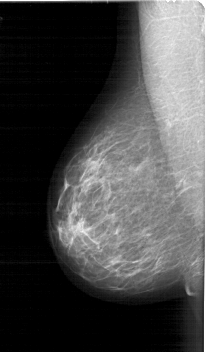

A_1764_1.RIGHT_MLO

LEFT_MLO LINES 5971 PIXELS_PER_LINE 3496 BITS_PER_PIXEL 12 RESOLUTION 43.5 NON_OVERLAY